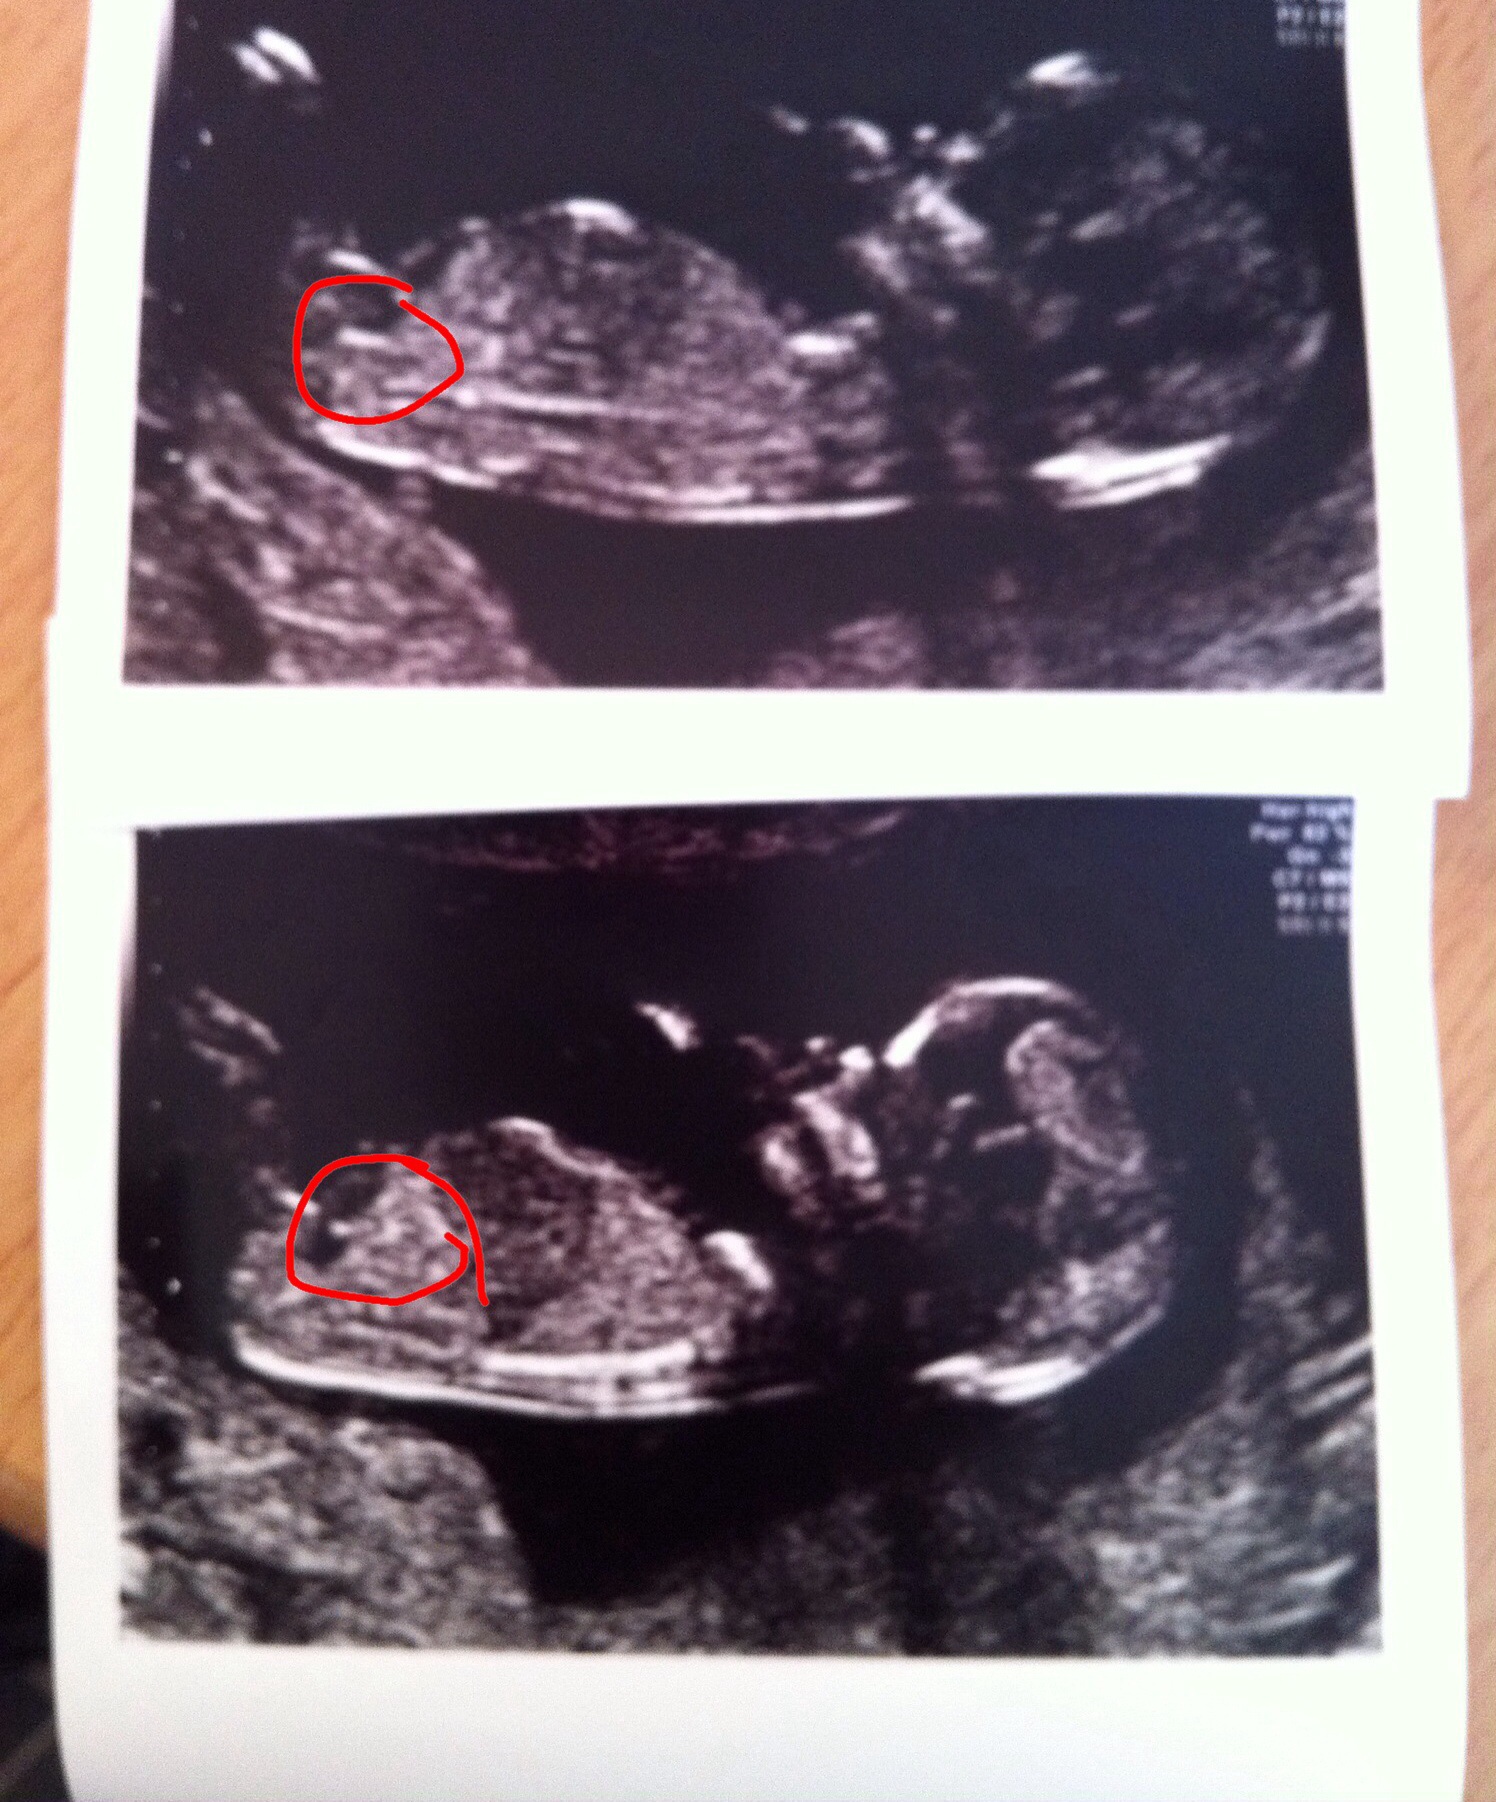

The nub is circled in the 2nd pic and you have a sweet little boy there.

I could definitely be wrong but it looks like it starts where you circled then continues riding to the left with a bulb at the end which means boy. A girl would have a more parallel nub with a fork at the end.

Looks like a little boy - nub is on the rise. How far along are you? x

Kasey the scan was took at 13+2. I see what you mean Abi but it looks like 2 completely different lines in the first pic do you agree? I've had crap nub shots on all my scans lol

13+2 I'm now 15 weeks though getting a private gender scan on the 8th , I've got 2 little boys was kinda hoping pink this time as think it might be our last lol